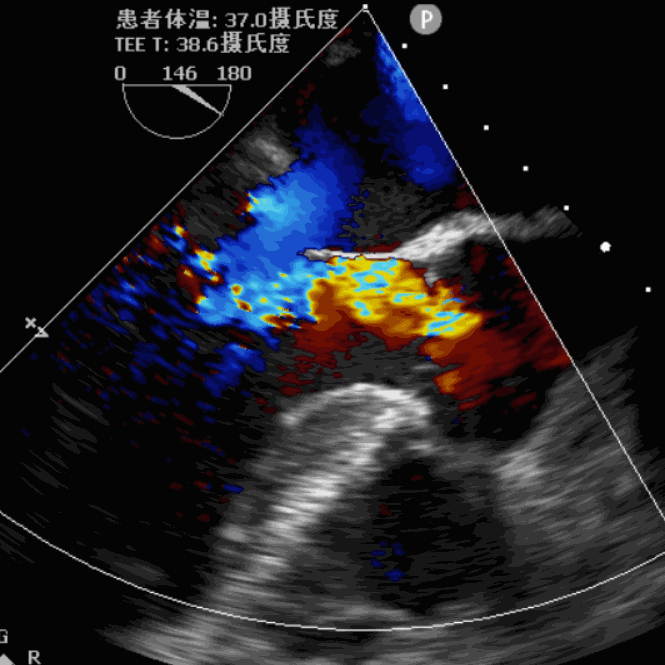

术前超声影像图

术后超声影像图

手术采用经心尖入路,对患者进行全麻后,在左侧心尖处微创手术切口仅3-4cm,在DSA及超声引导下植入JS-TAVI29#牛心包瓣膜,手术顺利完成。术前升主动脉根部测压86/47mmHg,左室压91/9mmHg,术后升主动脉根部测压87/49mmHg,左室压98/10mmHg。从导入器械到完成瓣膜置入,耗时9分钟。术后即刻主动脉瓣返流程度由术前大量返流转为消失,术后测得跨瓣峰值流速1.8m/s,平均跨瓣压差6mmHg,峰值跨瓣压差12mmHg。